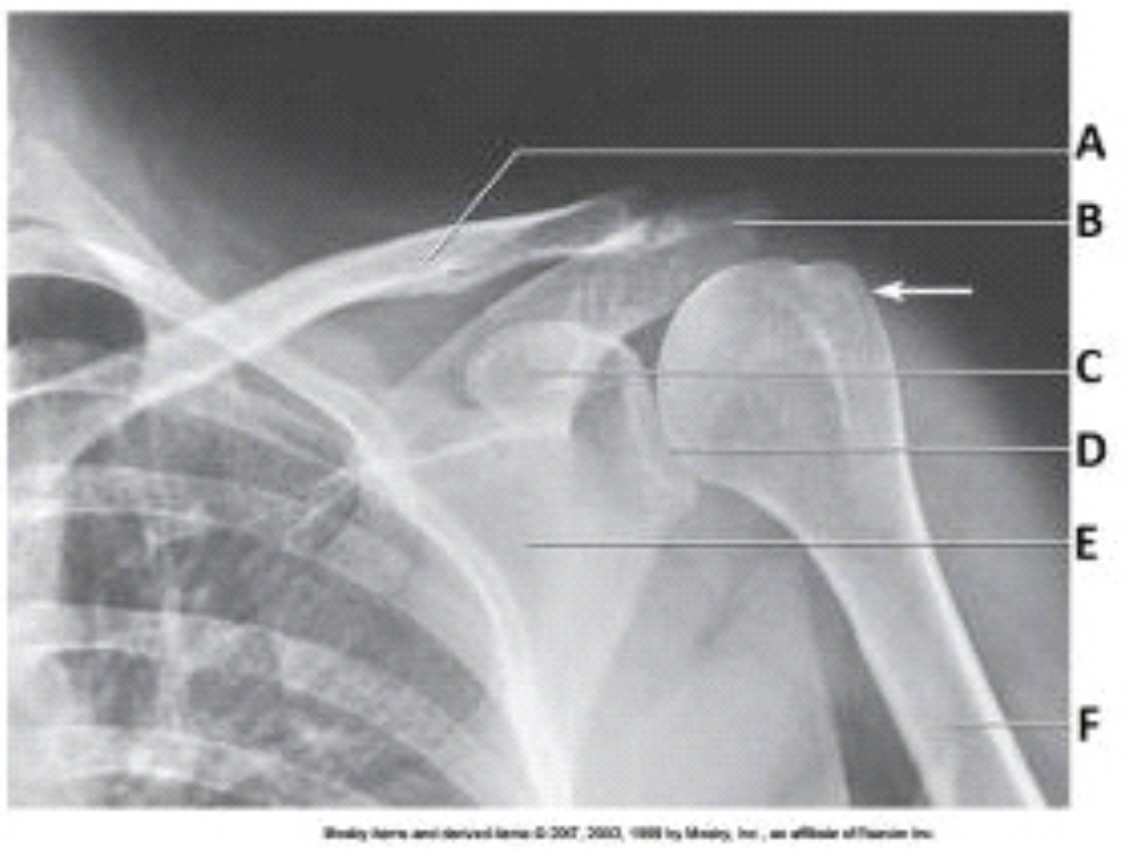

What projection (method) is demonstrated in the image below?

Inferosuperior axial (Lawrence)

What anatomy is labeled as letter A in the image below?

Lesser tubercle

What anatomy is labeled as letter C in the image below?

Coracoid process

What anatomy is labeled as letter D in the image below?

Acromion